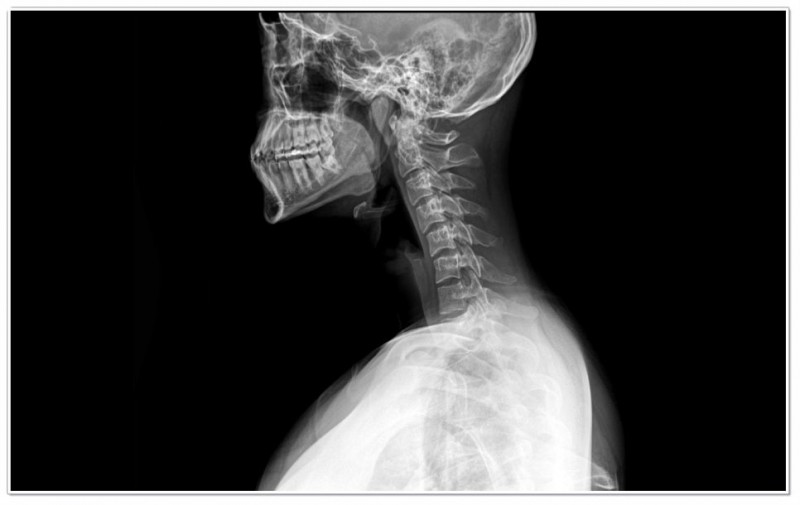

목디스크는 의학적으로 ‘경추 추간판 탈출증’이라고 부릅니다.

쉽게 말해, 목뼈 사이의 디스크가 제자리에서 밀려나 신경을 압박하는 상태를 뜻합니다.

디스크는 충격을 흡수하는 젤리 같은 조직인데,

자세 불균형이나 근육 긴장이 반복되면 손상되기 쉽습니다.